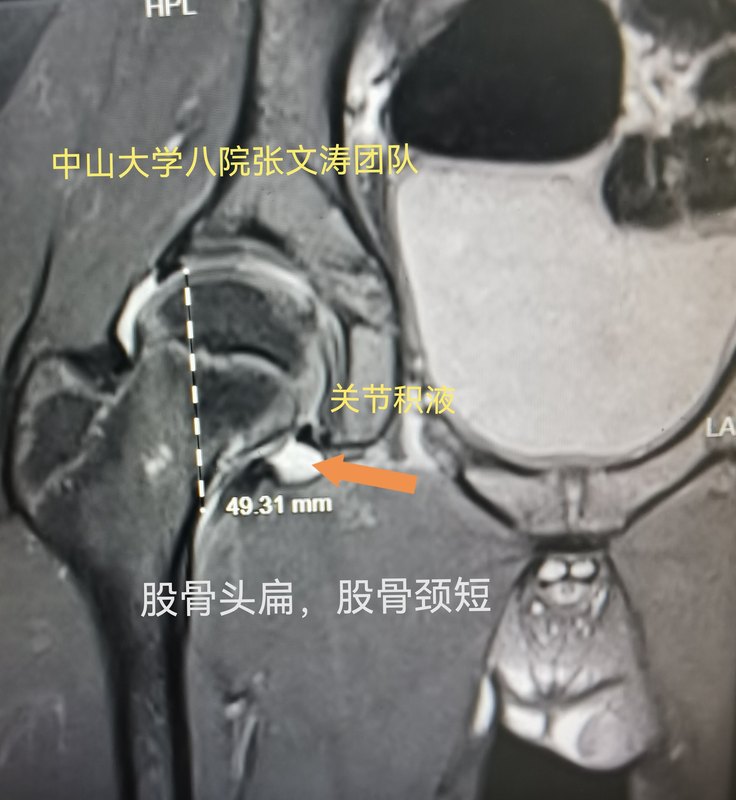

兒童髖關(guān)節(jié)積液,可能有后遺癥喲。

兒童感冒發(fā)燒拉肚子,都可能引起髖關(guān)節(jié)積液。因?yàn)楹⒆映3Uf同側(cè)膝蓋疼痛,就更容易漏診。如果核磁發(fā)現(xiàn)的早,一般經(jīng)過適當(dāng)治療,積液就消失了,大部分兒童也不會留下后遺癥。但是如果治療不及時積液反復(fù)發(fā)作,就會因?yàn)殛P(guān)節(jié)囊膨脹導(dǎo)致股骨頭外移,嚴(yán)重的甚至脫位。股骨頭外移,股骨頭和髖臼窩承重位置改變,對股骨頭生長板力學(xué)刺激改變就會引起形狀改變。比如股骨頭變扁變大,臼窩變淺變寬。就像下面的圖一樣。嚴(yán)重的成為扁平髖,輕度的可能成為髖發(fā)育不良。當(dāng)然髖發(fā)育不良還有遺傳等因素。

中山大學(xué)附屬第八醫(yī)院運(yùn)動醫(yī)學(xué)科科普號2023年12月24日261